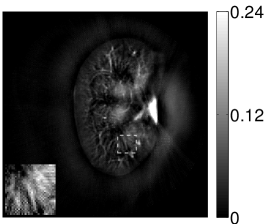

VI-E Results: kidney phantom

The images and EIRs reconstructed by use of the VP algorithm that was based on the 2D imaging model that neglected the SIR are shown in Figures 15 and 16. The latter figure contains results corresponding to different values for the regularization parameter . From Fig. 15, it can be observed that use of the conventional iterative method that utilized the measured EIR resulted in distortions and loss of details in the reconstructed images. Use of the VP algorithm improved the contrast and the details in the reconstructed images (Fig. 15(c) and 16(a)). Furthermore, the images reconstructed by use of the VP algorithm had a more uniform background.

In Figure 17, the results corresponding to use of the 3D imaging model that incorporated SIR effects are shown. The EIR estimated by the VP algorithm is also shown. In Figure 18, images and EIRs reconstructed by use of the VP algorithm with different regularization parameters values are shown.

Similar to the case described above where the transducer SIR was neglected, these results reveal that use of the VP algorithm can produce images with a cleaner background and enhanced spatial resolution than yielded by use of a conventional iterative algorithm that employed the measured EIR. For example, detailed information regarding the vessels near the organ’s periphery was better preserved by the VP algorithm than by the conventional iterative algorithm. These images corroborate our assertion that the VP algorithm can significantly reduce the artifacts and distortions in the reconstructed image. It is also worth pointing out that, unlike the numerical phantom studies, the artifacts and distortions in the images may be caused not only by the inaccurate EIR but also by other factors, such as neglecting acoustic heterogeneities and the variation of the EIRs among the elements of the transducer array. In such cases, the EIR estimated by the VP algorithm represents an effective system impulse response that minimizes the inconsistency between the measured data and the imaging model.